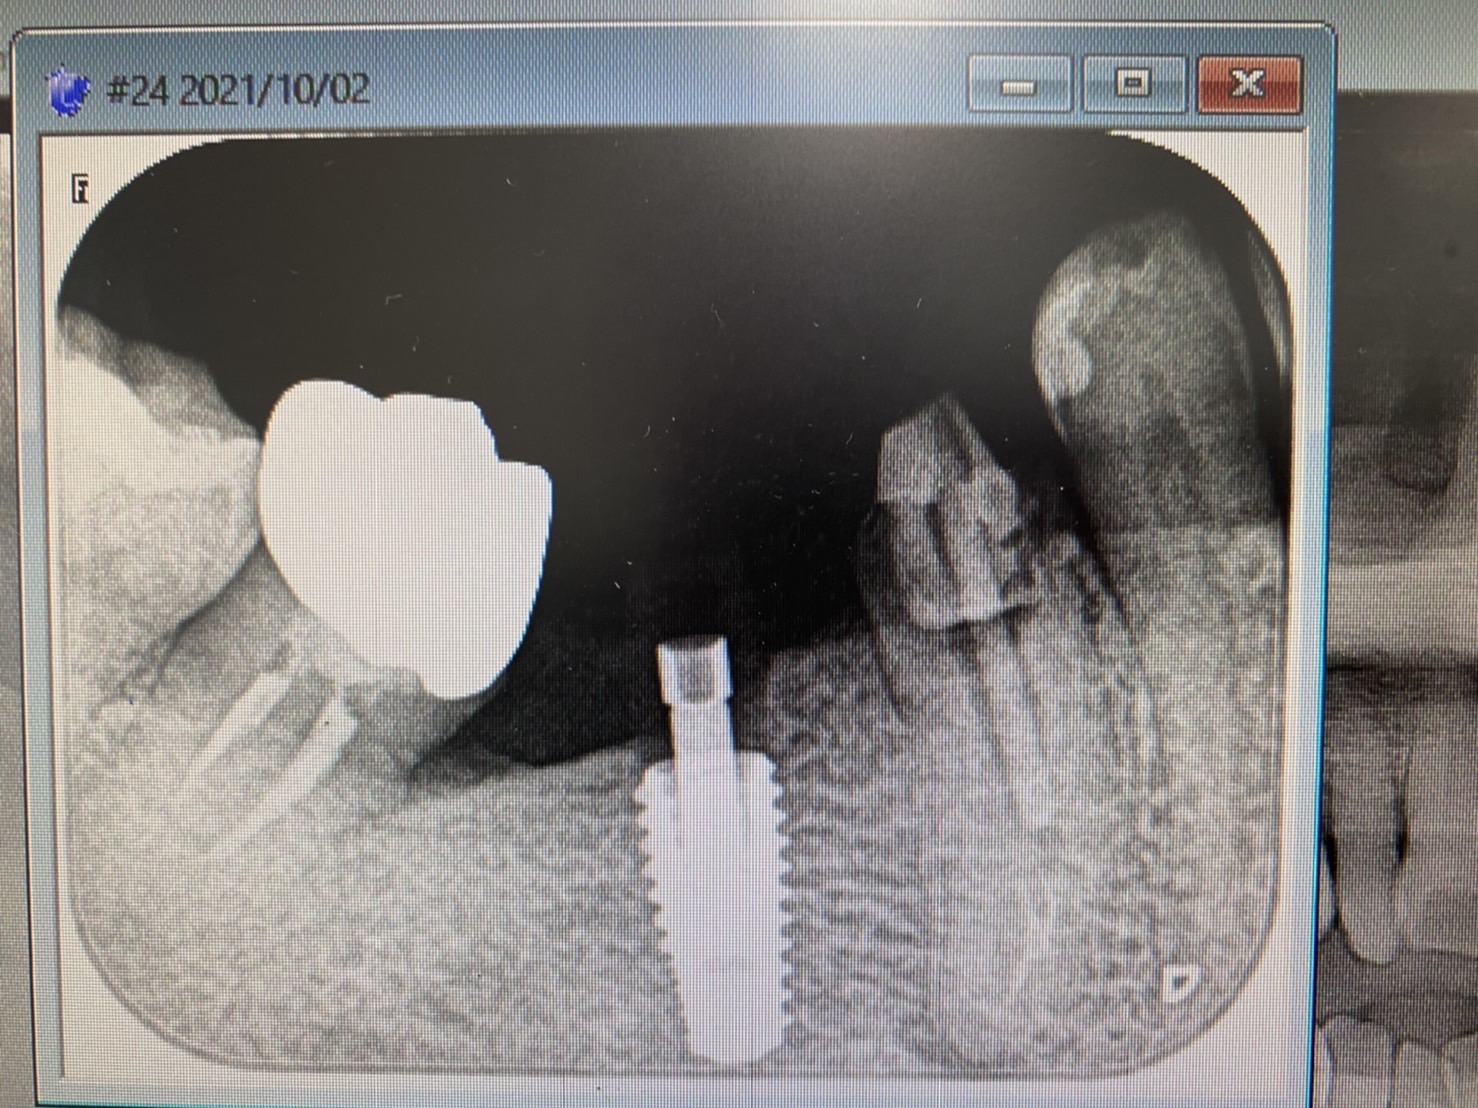

今朝は、下前歯の歯周再生治療からスタート

画像からも判るように、骨吸収が著しくこのままでは、抜歯に!

再生治療を提案し、リグロースを使用。

更には上結節より結合組織採取し歯肉厚み、高さを増し(バイオタイプの変更とルートカバーも同時に行う)、CK-2ナイフを使用して袋を大きくするようにして無事終了。